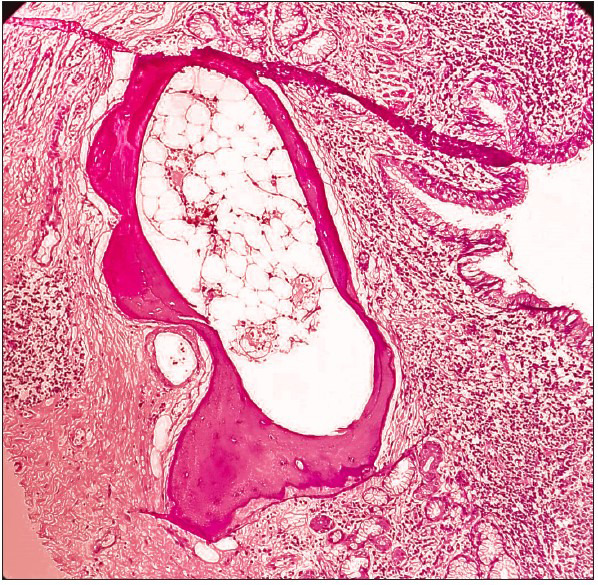

Bronchial involvement in pulmonary actinomycosis is rare and has been reported in the literature rarely. However, these reports describe endobronchial actinomycosis secondary to foreign body aspiration (for example, a fish bone). Our case did not have any history or clinical evidence suggesting foreign body aspiration, which makes it even more rare. A 55-year-old woman presented with complaints of on and off haemoptysis and cough for three weeks. In view of the haemoptysis and consolidation seen on imaging, a bronchoalveolar lavage was done and sent for cytological assessment. Few atypical cells with nuclear hyperchromasia and prominent nucleoli were noted. In view of the persistent haemoptysis, worsening symptoms, and non-resolution of the consolidation despite antibiotics, and the finding of atypical cells, segmental resection was done. A final diagnosis of bronchiectatic actinomycosis with osseous metaplasia was given. The patient was started on prolonged antibiotics with good response and recovery. Other risk factors associated with pulmonary actinomycosis include alcoholism, diabetes, haematological diseases, human immunodeficiency viral infection, use of immunosuppressants, and rarely chronic lung diseases, such as bronchiectasis. Our case had this rare association of bronchiectasis with bronchial actinomycosis. Bronchiectatic actinomycosis is a rare infection and it can mimic several lung disorders like unresolving pneumonia, pulmonary tuberculosis, foreign body, and even lung tumours. The pathologists and clinicians should be aware of this entity and thus help in the early diagnosis and better management of patients with this disease.